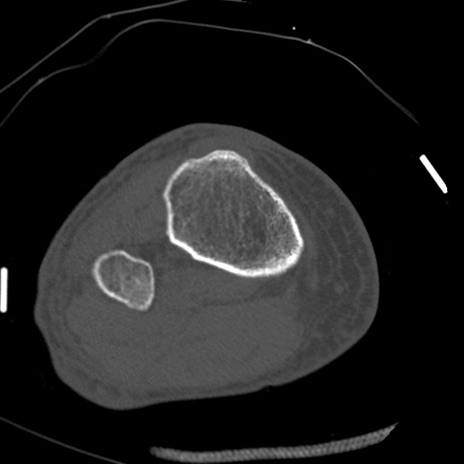

症例28 右膝関節CT(横断像)

右膝関節CT